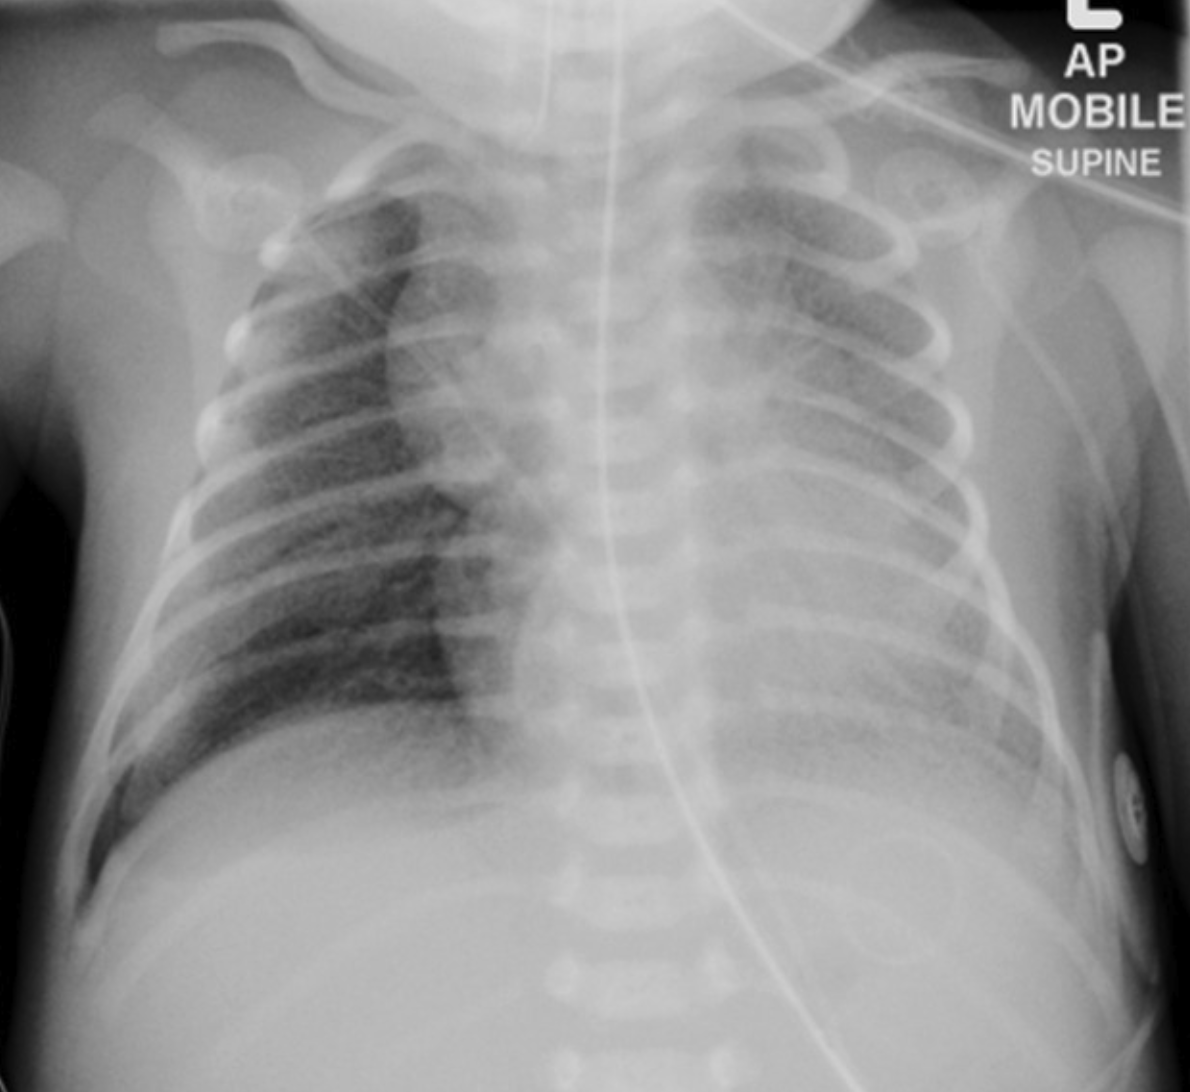

( Neonatal RDS X-Ray)